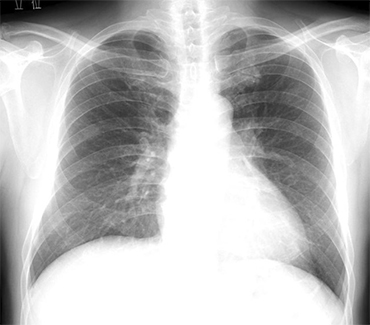

単純X線

最も歴史のある画像診断法ですが、今なお画像診断の基本となる重要な検査です。当科では胸部、腹部、骨、関節、乳腺をはじめとする幅広い領域の単純X線を読影しています。

当教室が長年にわたって研究開発に取り組んでいる診断支援技術の一つに経時差分法があります。下図に、コンピュータ支援診断法の一例を示します。経時的差分法というコンピュータ画像処理により、撮影時期の異なる2枚の単純X線写真の差分を取り、正常構造を消去する事により、経時的変化を強調して描出する手法を示しています。通常の胸部単純X線写真だけではわかりにくい病変も、前回の写真とのデジタル差分画像を取得することにより、見逃すことなく診断できるようになりました。